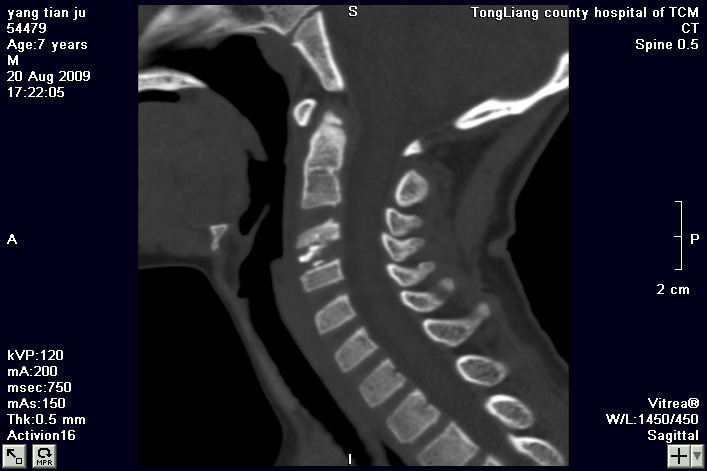

标题: PED2853:颈3/4椎间盘内高密度钙化灶,请各位会诊. [打印本页]

标题: PED2853:颈3/4椎间盘内高密度钙化灶,请各位会诊.

患儿,7岁,颈部疼痛3天,颈部活动受限.

本例应该是典型的儿童钙化性椎间盘病。

儿童钙化性椎间盘病发病年龄多在5~12岁,男女比例相当,大多数患儿发病主要表现为颈部疼痛,伴活动受限。少数有吞咽不适或肢体瘫痪。有一部分患儿无症状,是在其它检查时发现。病因尚不完全明了,可能的有:1、感染。2外伤。

儿童颈椎椎间盘钙化系一良性自限性疾病,可见于颈、胸、腰椎,以颈椎为多发,腰椎少见,多为单发。钙化位于髓核,也可累及软骨板和纤维环引起钙化主要发生于c 4~7  的髓核位于椎间隙正中或偏后,少数向前疝出,以后部多见,呈梭状、盘状、团块状或半环状;(2)颈椎生理曲度变直,椎间隙正常或增宽;(3)相邻椎体可变扁,局部凹陷变形,椎体前下缘鸟嘴状增生,或呈钳口状改变,椎前软组织增厚及环枢椎半脱位;(4)ct可清晰显示椎间盘髓核 位置的钙化灶及经破裂的纤维环向椎管内突出。(5)mri,钙化在t1及t2加权像上均呈低信号,并可见脊髓组织内异常信号。